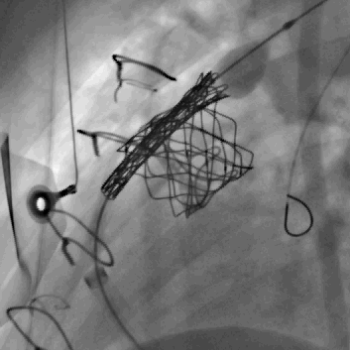

Centrum komplexní péče o vrozené srdeční vady v dospělosti vzniklo  v roce 2015  díky spolupráci  Centra kardiovaskulární a transplantační chirurgie s Interní kardiologickou klinikou Fakultní nemocnice  Brno a nabízí zcela komplexní péči o dospělé nemocné s vrozenou srdeční vadou. Portfolia jednotlivých pracovišť se navzájem doplňují.  Centrum poskytuje ambulantní sledování pacientů se všemi typy vrozených srdečních vad, neinvazivní a invazivní diagnostiku včetně transesofageální echokardiografie s využitím 3D zobrazení.  Centrum kardiovaskulární a transplantační chirurgie Brno provádí operace, reoperace a  intervenční výkony u vrozených srdečních vad a současně se věnuje chirurgické léčbě pokročilého srdečního selhání vč. implantace mechanických srdečních podpor a transplantace srdce ( Tým lékařů , seznam prováděných operačních a intervenčních výkonů).  V rámci Interní kardiologické kliniky FN Brno poskytuje invazivní  řešení arytmií ( radiofrekvenční ablace, kardiostimulace vč. resynchronizační léčby), některé intervence (uzávěry defektů septa síní) , organizaci nekardiálních operací a péči o gravidní včetně porodu probíhají v rámci Interní kardiologické kliniky FN Brno.   Návaznost na kardiologii dětského věku je zajištěna spoluprací s Fakultní dětskou nemocnicí v Brně.  Ambulantní péče probíhá na obou klinikách paralelně.